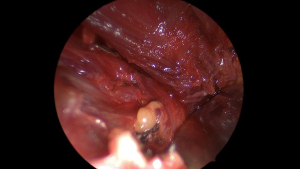

NIR was performed using the ICG rigid endoscope with Rubina camera head (Karl Storz, Tuttlingen, Germany). The endoscopic system utilizes a filter to switch between white light and NIR light emitted from a light-emitting diode (LED) source (Figures 1-3). The camera was used intermittently during key portions of the case to assist dissection and preservation of parathyroid tissue where in doubt, as well as for evaluation of the extracted thyroid specimen to identify any inadvertently removed parathyroid glands. Any identified glands were then reimplanted. The final specimen was then submitted to the same anatomical pathology laboratory for analysis.

Some studies evaluating the effectiveness of NIR have primarily used the technology to examine the extracted thyroid specimen for inadvertently removed parathyroids, thereby allowing the opportunity to reimplant (12,13). In our institution, we utilize the technology throughout the operation to assist in confirmation of parathyroid tissue in situ. We have found value in instances where parathyroid tissue may be difficult to differentiate from nodal tissue, fat, atypical thyroid nodular tissue or found in an intracapsular position. Figure 5 demonstrates visual contrast between fat and parathyroid tissue, allowing intra-operative differentiation. This may especially be useful in cancer cases where resection margins are paramount, as is removal of any suspicious extra-thyroidal tissue. The NIR camera is yet to be trialled as an adjunct in central neck dissection, but we anticipate it to be useful in improving efficiency and reducing inadvertent parathyroidectomy while maintaining oncologic outcome. If there is tissue suspected to be normal parathyroid in the central nodal compartment, use of the NIR camera would allow for quick identification and confirmation. This may minimize reliance on frozen section analysis and avoid the risk of retained disease or unnecessary parathyroid gland sacrifice when in close proximity to pathologic lymph nodes. In this study, of the 13 patients who underwent central neck dissection (all by naked eye detection only), there were seven cases of inadvertent parathyroidectomy. We believe that NIR may play an important role in balancing parathyroid preservation with thorough resection of malignancy.